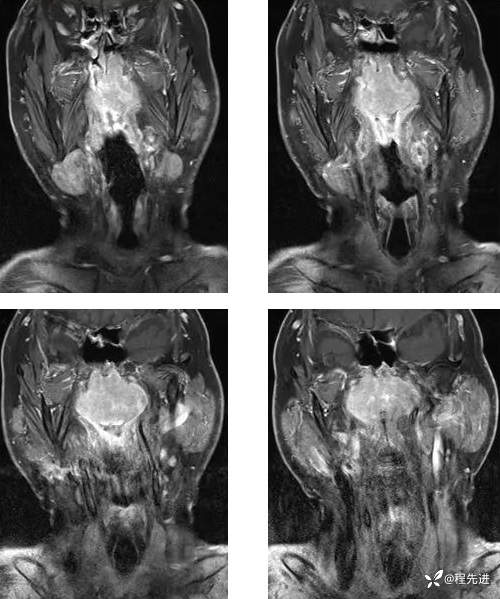

T1增强: